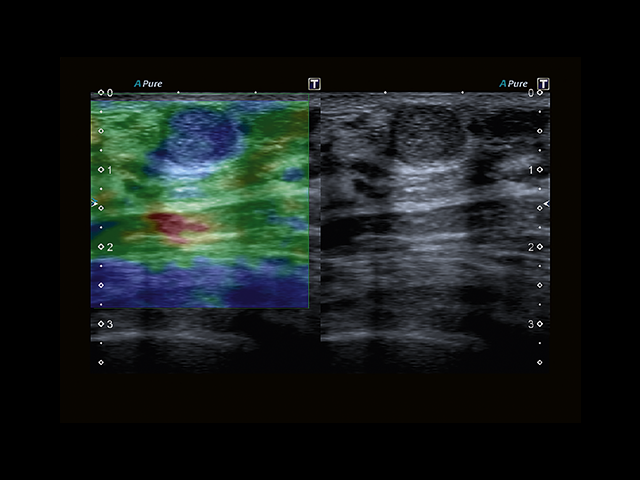

• MicroPure. Высокотехнологичное решение в области выявления микрокальцификатов – маркеров новообразований злокачественного типа. Маркеры идентифицируются путем изучения затененных изображений целевого участка. Микрокальцификаты отображаются в виде белых пятен.

• SMI. Опция, упрощающая визуализацию микроциркуляторного русла. С ее помощью обследуются сосуды с низкой интенсивностью кровотока, изучаются наиболее тонкие структуры. SMI упрощает диагностику новообразований, минимизирует вероятность ошибки.